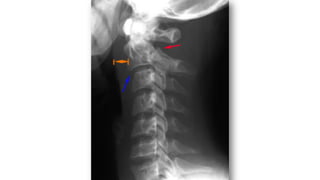

PARTES BLANDAS

• Valorar hematoma por FX

valorar espacios:

• E. Nasofaríngeo (C1)=10mm

• E. Retrofaríngeo (C2-C4)= 5-7mm

• Retrotraqueal (C5-C7)= 22mm ó

(< 1 cuerpo vertebral).

Nasofaríngeo

Retrofaríngeo

Retrotraqueal